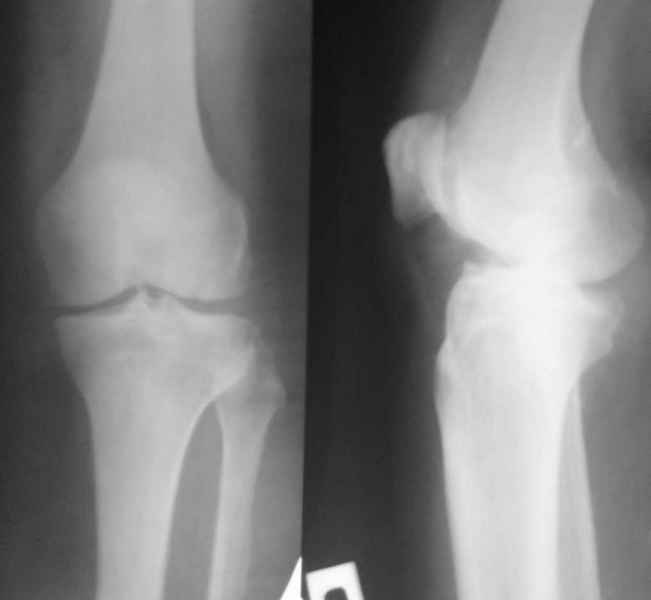

В феврале 2007 года пациентке выполнено эндопротезирование коленного сустава.

Через 1 месяц после операции объем движений 90 градусов, через 2 месяца 60, через 3 - 40, через 5 - качательные движения.